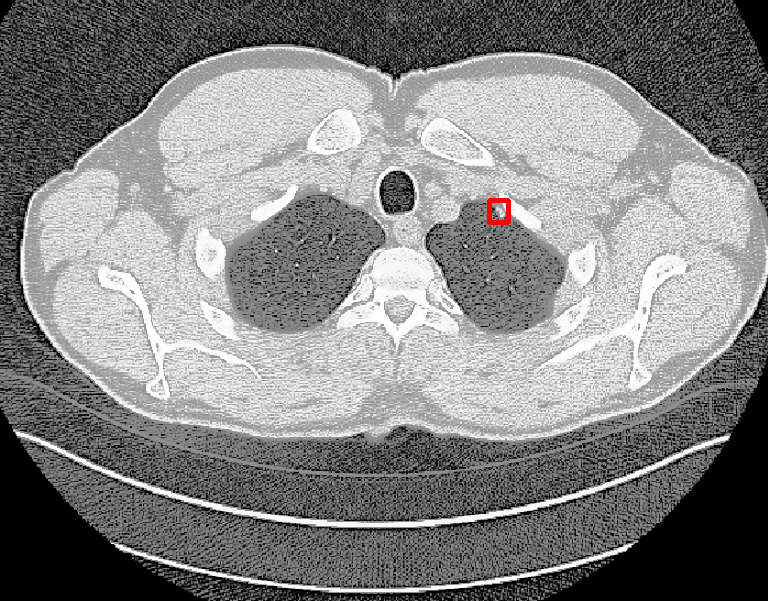

| (a) Ground Truth | (b) Faster R-CNN | (c) FPN | (d) Proposed |

In real-world scenarios, body lesions usually have arbitrary size. For instance, in the DeepLesion [14] dataset, the lesion size ranges from 0.21 mm to 342.5 mm. Since most of the established CNNs are not robust to handle such spatial scale variations, they have unpredictable behavior in the varying cases. As shown in Fig. 1, both Faster R-CNN and FPN fail to detect tiny lesions in the first row, while they produce small false positive lesions around the actual large lesion locations in the second and third rows.